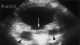

Dilated bladder

Urinary retention is an inability to completely empty the bladder. Onset can be sudden or gradual. [Source: Wikipedia ]